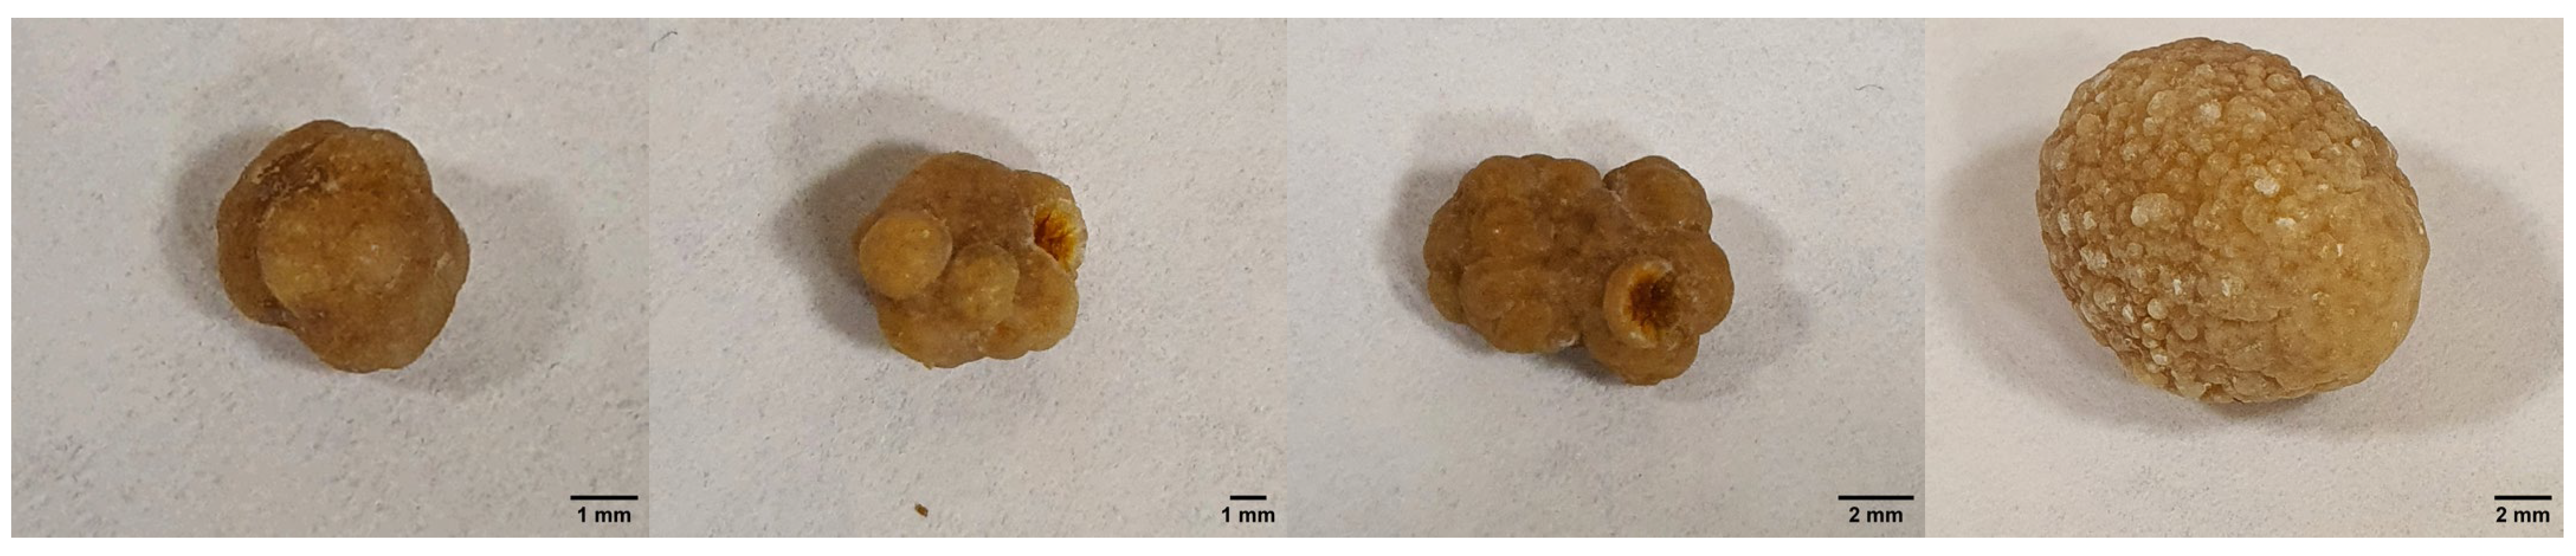

2.1. Results of Clinical Case Investigation

2.1.1. Results of X-ray and Electron Microscopic Studies

4.1. Clinical Case

4.2. X-ray Microtomography (XMCT)